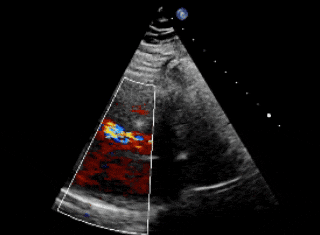

术前超声、造影

超声下可见右冠窦与右心房相通,主动脉短轴切面示类似膜周部室缺